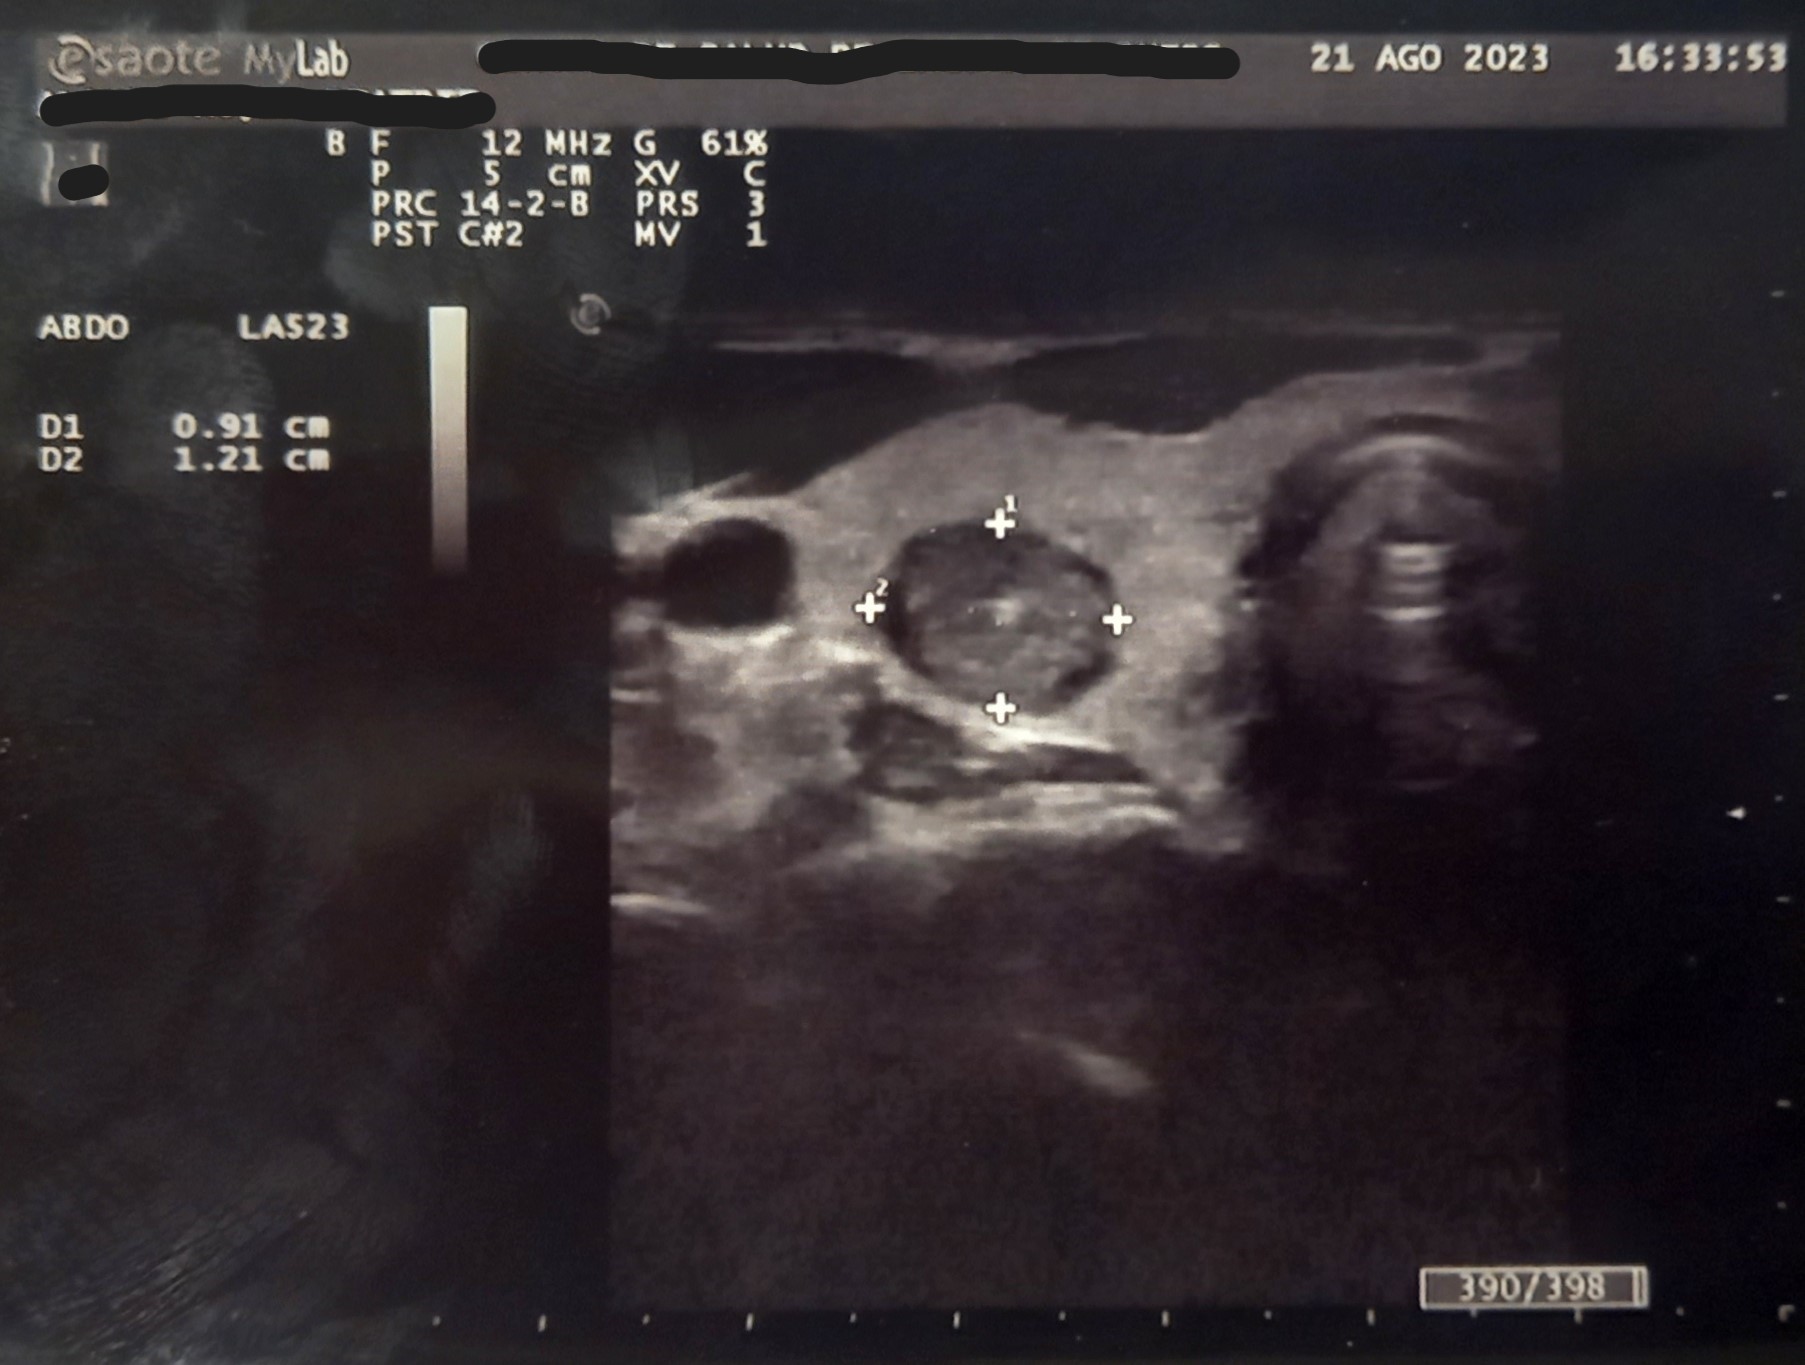

Ecografía en consulta de Atención Primaria. Se observa quiste completo en lóbulo tiroideo derecho, No condiciona aumento importante de tamaño de lóbulo: Dimensiones 14*22*41 mm. Zonas con hiperecogenicidad difusa. Nódulo de características complejas. Ecogenecidad heterogénea zonas anecoicas/hipoecoicas y calcificaciones múltiples. Escala TIRADS: 3.